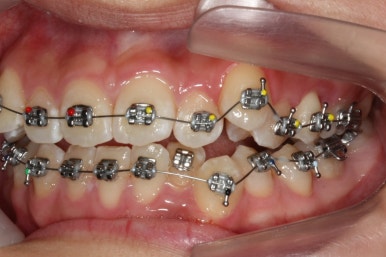

장치를 부착하였습니다.

부산교정전문의 키다리아저씨치과에서 이번에 사용한 장치는 메탈장치이며, 가장 기본적이고 역사가 오래된 장치가 되겠습니다.

우선 위쪽 작은 어금니 부터 발치하였습니다.

송곳니 바로 뒤쪽의 작은 어금니를 뽑은 것을 보실 수 있겠습니다.

이제는 아래쪽 작은 어금니도 뽑았습니다.

교정치료를 시작한지 3개월 밖에 지나지 않았을 시점인데도 벌써 덧니가 많이 가지런해졌습니다. 치아는 자리만 확보되면 쉽게 가지런해질 수 있습니다.

가지런해지지 않았던 아래 앞니 하나도 금새 가지런해졌습니다.